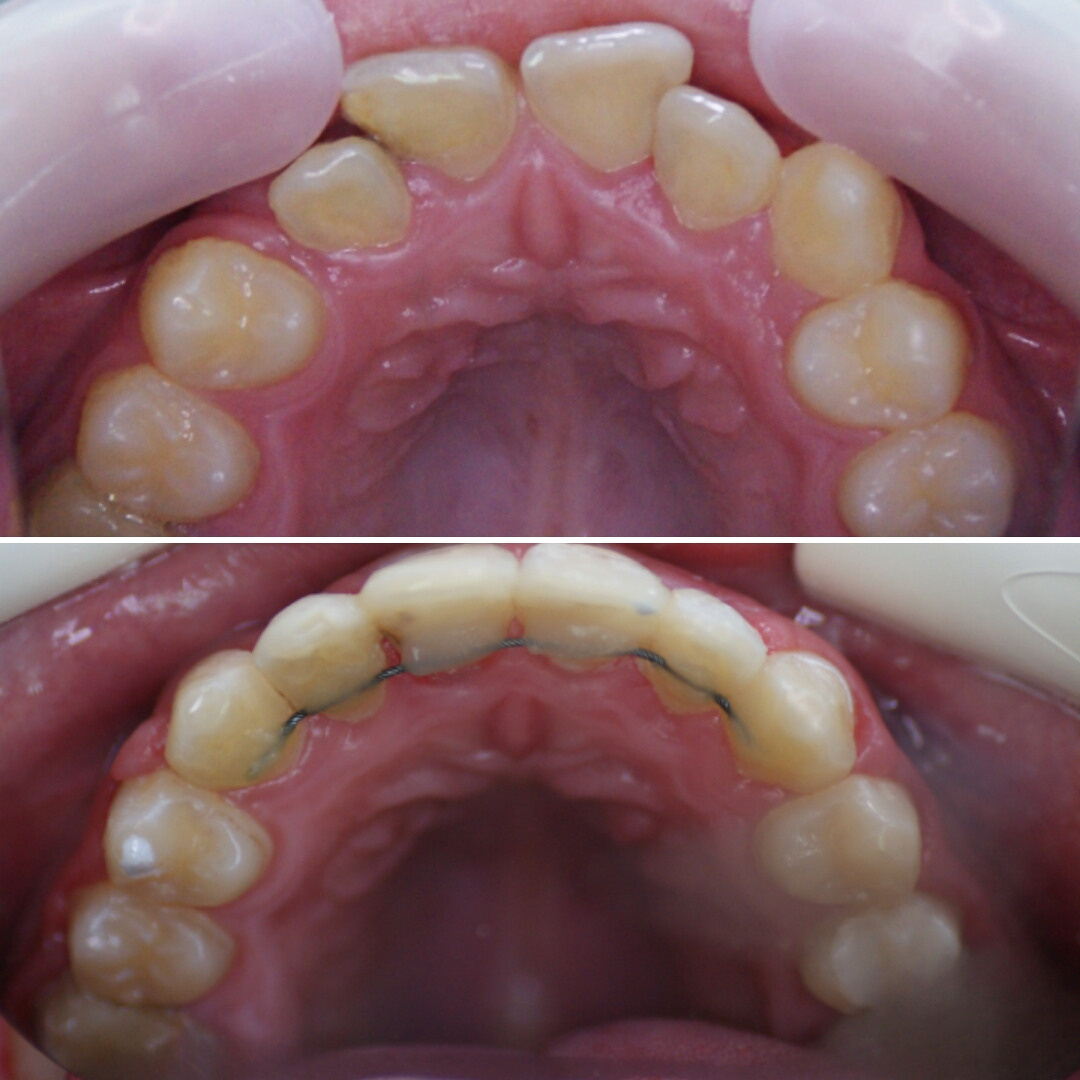

ЧАСТЬ 1. АППАРАТАТ МАРКО РОСА (Marco Rosa) или аппарат для быстрого нёбного расширения. Это ортодонтический аппарат, названный так в честь своего создателя - итальянского доктора ортодонтии Marco Rosa.

▶️ Аппарат нужен для расширения верхней челюсти если она сужена.

❓ Как аппарат расширяет челюсть?

▶️ Аппарат устанавливается на верхнюю челюсть, у него есть пластмассовый базис, в который встроен винт. При раскручивании винта, половинки аппарата раздвигаются , передавая силу давления винта на зубы и твёрдое нёбо, верхняя челюсть расширяется.

КОНСТРУКЦИЯ АППАРАТА МАРКО РОСА

1️⃣ ВИНТ ХАЙРЕКС. Создаёт расширяющее усилие.

2️⃣ МЕТАЛЛИЧЕСКИЕ ЛАПКИ. Это дополнительные элементы фиксации, которые упираются в молочные клыки, создают точки приложения силы к зубному ряду.

3️⃣ КОЛЬЦА НА МОЛОЧНЫЕ МОЛЯРЫ. Обеспечивают фиксацию аппарата на опорных зубах с помощью специального стоматологического клея.

4️⃣ ПЛАСТМАССОВЫЙ БАЗИС (пластинка). Объединяет все элементы в единую систему и передаёт расширяющее усилие винта на нёбо.

5️⃣ ДОПОЛНИТЕЛЬНЫЕ ЭЛЕМЕНТЫ (крючки для лицевой маски)

*️⃣ Спанч Боб и Патрик😀

Аппарат Марко Роса (Marco Rosa) - маленький невидимый помощник в больших ортодонтических делах💗